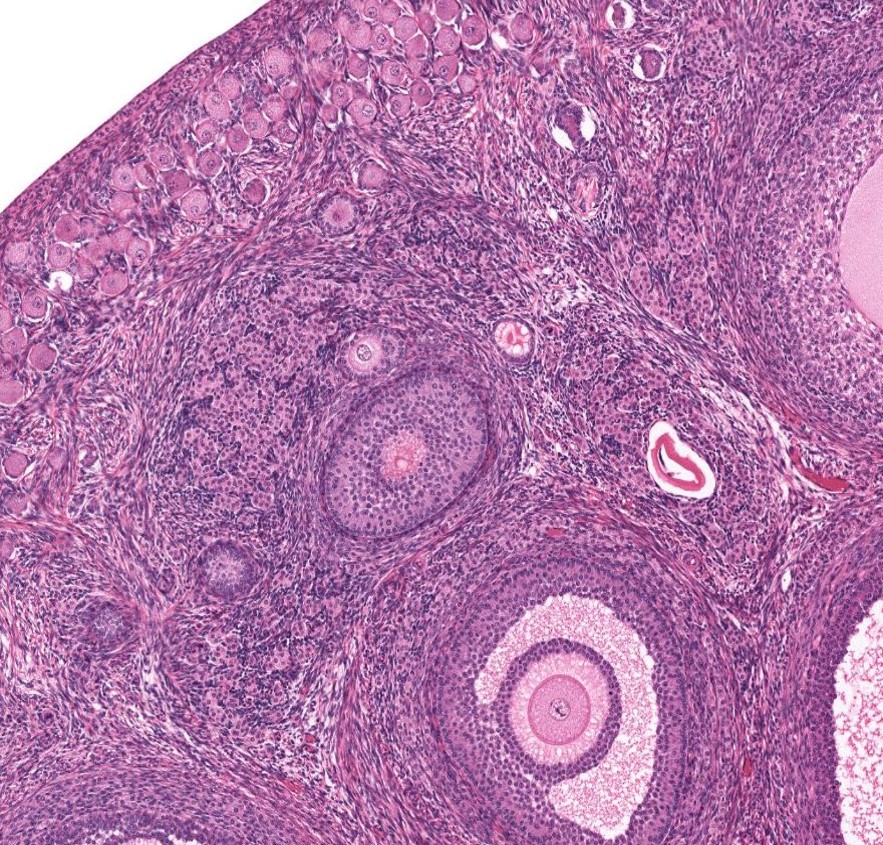

Ovário - folículo primordial

Ovário - folículo secundário

Ovário